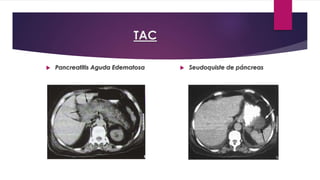

TAC

 Pancreatitis Aguda Edematosa  Seudoquiste de páncreas

TAC  PancreatitisAguda Edematosa  Seudoquiste de páncreas